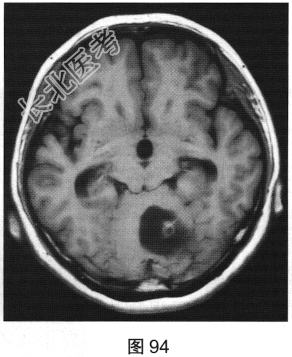

- [材料题] 患者女性,51岁,因“头晕、恶心进行性加重1个月余,伴呕吐5小时”就诊。患者于1个月前出现头晕症状,伴恶心,无视物旋转、头痛、走路不稳,无言语改变、意识障碍。患者症状反复发作并进行性加重,2周前间断出现走路不稳,似醉酒样步态,倒向左侧;5小时前出现头晕、恶心,并呕吐胃内容物,站立不稳。既往有高血压病史3年,血压控制尚可。查体:轮椅推入病房,可见步态不稳,神志清楚,应答正确,无吟诗样及爆炸样言语,遵嘱活动,双侧瞳孔等大正圆,对光反射灵敏,四肢活动可,肌力、肌张力未及异常,指鼻试验、双侧轮替试验阴性,双侧跟膝胫试验欠稳准,双侧膝反射及跟腱反射正常,双侧病理征未引出,闭目难立征不能配合。实验室检查:外周血白细胞计数15.29×109/L,中性粒细胞百分比92.1%,二氧化碳18.8mmol/L,血糖7.05mmol/L;心肌酶、凝血试验正常。

- 多项选择题2.[提示]患者行CT及MRI检查,如图90~图95所示。CT及MRI上的阳性影像学表现包括( )

A、MRI示右侧囊实性病变

B、病变实性成分增强扫描可见明显强化

C、MRI示左侧囊实性病变

- 多项选择题3.根据患者病史及影像学检查,提示其可能诊断为( )

A、血管母细胞瘤

E、脑视网膜血管瘤病

F、小脑